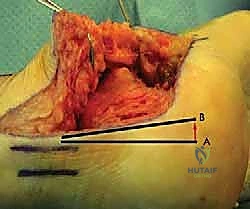

- إعادة بناء الأوتار والأربطة:

في حالة تضرر الأوتار الشظوية بسبب الانحشار الطويل، يتم تنظيفها وإصلاحها وإعادة توجيهها في مسارها السليم لضمان استعادة القوة العضلية للقدم.